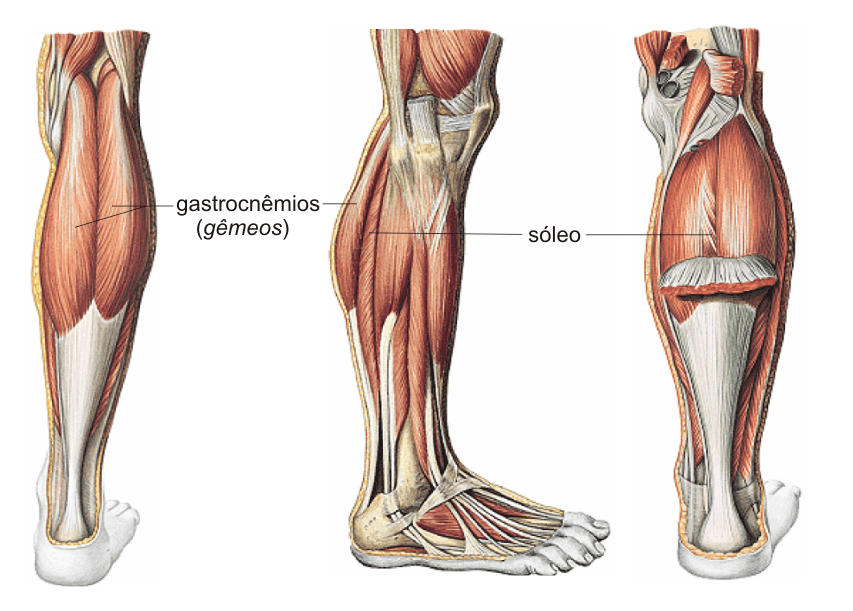

Pode parecer surpreendente, mas os seres humanos têm, de fato, uma espécie de “segundo coração” localizado nas pernas. Conhecido como músculo sóleo, essa estrutura vital, localizada na panturrilha, desempenha um papel crucial para a saúde do corpo, agindo como uma bomba natural que ajuda a impulsionar o sangue de volta ao peito.

Esse mecanismo, chamado de “bomba da panturrilha”, funciona de forma plena apenas com o movimento. Seja ao caminhar, ao correr ou até mesmo ao mexer os pés enquanto estamos sentados, a contração muscular das panturrilhas é o que garante que o sangue desoxigenado retorne ao coração de maneira eficiente.